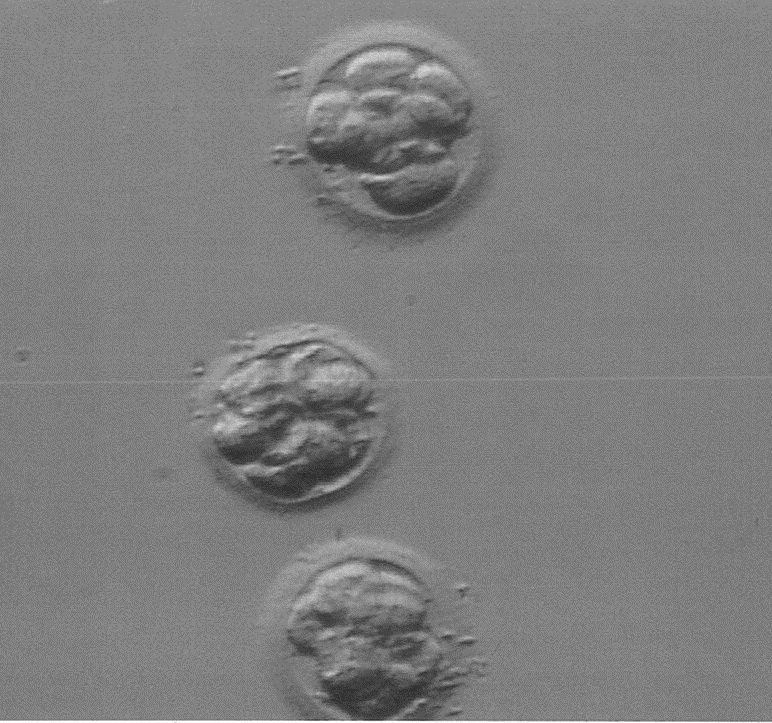

ca. 73 Stunden nach der PU (wann die eigentliche ICSI gemacht wurde weiß ich allerdings nicht) bekam ich drei Embryonen zurück. Laut Arzt 6-8-Zeller, so genau könne man das nicht sagen und die Qualität wäre sehr gut bis gut. Ich als Laie kann auf dem Foto aber nur jeweils 6 Blastomeren erkennen und frage mich, ob einer der Embryonen überhaupt mehr als 6 Zellen hatte. Wie würden Sie die Embryonen von der Zellteilung und der Qualität (A-D) einschätzen?

alle drei Embryonen sehen gut aus, soweit vom Photo erkennbar, würde ich sie mit B einstufen.

Der obere und der untere Embryo sind 6-Zeller, der mittlere ein 8-Zeller.